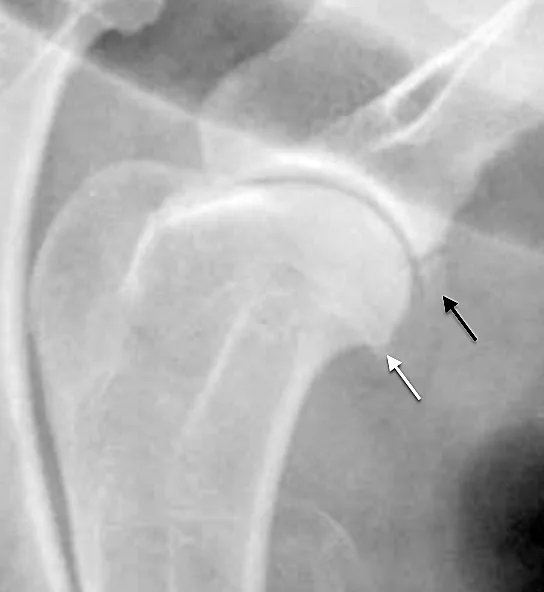

FIGURE 1

Lateral radiograph of a normal shoulder showing the biceps origin (blue circle) and course (blue bar)

The proximal biceps tendon originates from the supraglenoid tubercle and traverses the cranial aspect of the proximal humerus in the intertubercular groove, where, at the musculotendinous junction, it forms the biceps muscle. Mineralization may occur at any point along the length of the tendon but is commonly noted both superimposed with the groove and at the tendon origin (Figure 1).1